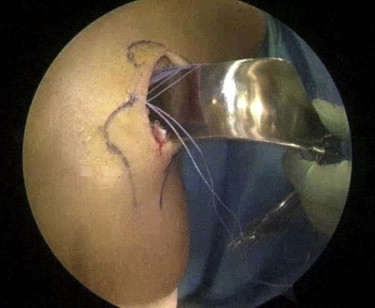

Fig 6.

Arthroscopic view of an unstable discoid lateral meniscus after saucerization and inside-out suture repair (arrow) of the posterior horn in a left knee, viewing through an anterolateral portal.